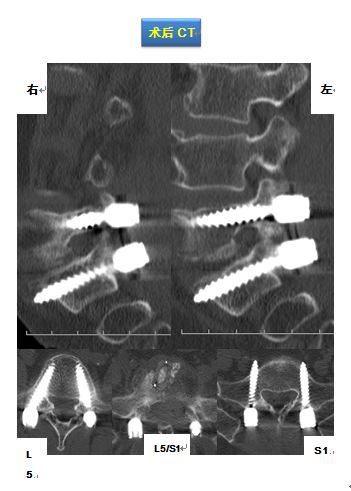

该手术在梁徳主任指导下由江晓兵副教授按照标准化流程顺利完成,将致压髓核进行了彻底摘除,神经压迫顺利解除。术后复查如下:

术后影像学提示可见L5/S1突出物已被完全摘除,神经减压良好。

腰椎X线正位L5/S1间隙塌陷;核磁可发现L5/S1椎间盘后方偏右突出并压迫神经,同层面椎管狭窄。

治疗方案:后路L5/S1减压植骨融合内固定术

该手术在梁徳主任指导下由江晓兵副教授按照标准化流程顺利完成,将致压物进行了彻底摘除,神经压迫顺利解除,并进行植骨及钉棒系统内固定。术后复查如下: